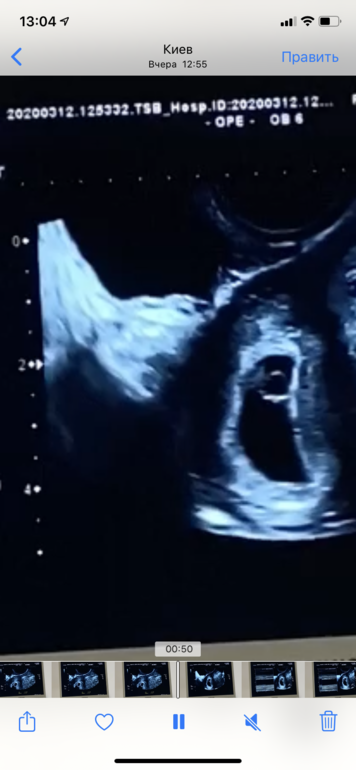

По узи сказали срок 6+3,

Нашли сердцебиение 💗 153уд/м

Протокол:

Матка 55*48*56

Плодное яйцо 33*23*25

Ктр 6.0мм

ЖМ 4,6мм

Хорион толщина 4,5мм

ЖТ 22мм диаметр

Прикреплю скрин 😁